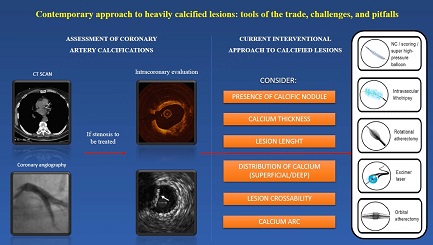

Contemporary approach to heavily calcified lesions: tools of the trade, challenges, and pitfalls

Coronary artery calcifications (CAC) affect more than 90% of men and more than 67% of women older than 70; the spread is mainly due to the high occurrence of major cardiovascular risk factors. The presence of CAC can be detected by several noninvasive and invasive methods like computed tomography (CT), coronary angiography (CA), Intravascular Ultrasound (IVUS), and Optical Coherence Tomography (OCT), with each system providing different information that can be used in the treatment strategy of CAC. Several devices can modify calcium during PCI: high-pressure non-compliant balloons, cutting/scoring balloons, atheroablative technologies, and intravascular Lithotripsy (IVL). Each technique has advantages and disadvantages that every interventional cardiologist should know to perform an optimal PCI and to achieve the best result and clinical outcome. This is a narrative review that aims to illustrate the contemporary management of CAC, focusing on the available techniques to assess calcifications and their novel advancements and explaining the existing tools to treat CAC with a focus on their significant challenges and pitfalls.

Coronary artery calcifications (CAC) are increasing because of the high prevalence of risk factors and advanced age. The bulk of moderate to severe CAC in the population undergoing percutaneous coronary intervention (PCI) is estimated to be around 32%, of which 6%-20% is considered severe[1]. The availability of different and ever more sophisticated systems to detect CAC, together with the development of several tools able to modify calcium, allows treating calcific stenosis and performing PCI in most patients. Recent studies demonstrate PCI optimal results and better outcomes, also in the long term. This narrative review examines CAC’s contemporary assessment and treatment, focusing on the pitfalls and challenges of debulking calcific lesions.

Characterization of calcium lesions is essential to choosing the adequate device; nowadays, several algorithms suggest which tool to treat CAC based on calcium characteristics [Figure 6]. However, in some cases, a single system to modify calcium is insufficient, because every device has advantages and disadvantages [Table 1]. Thanks to the growing operator’s confidence and expertise, more than one device is increasingly used to treat heavy coronary calcification in a synergistic combination that allows optimal lesion preparation to facilitate stent delivery.